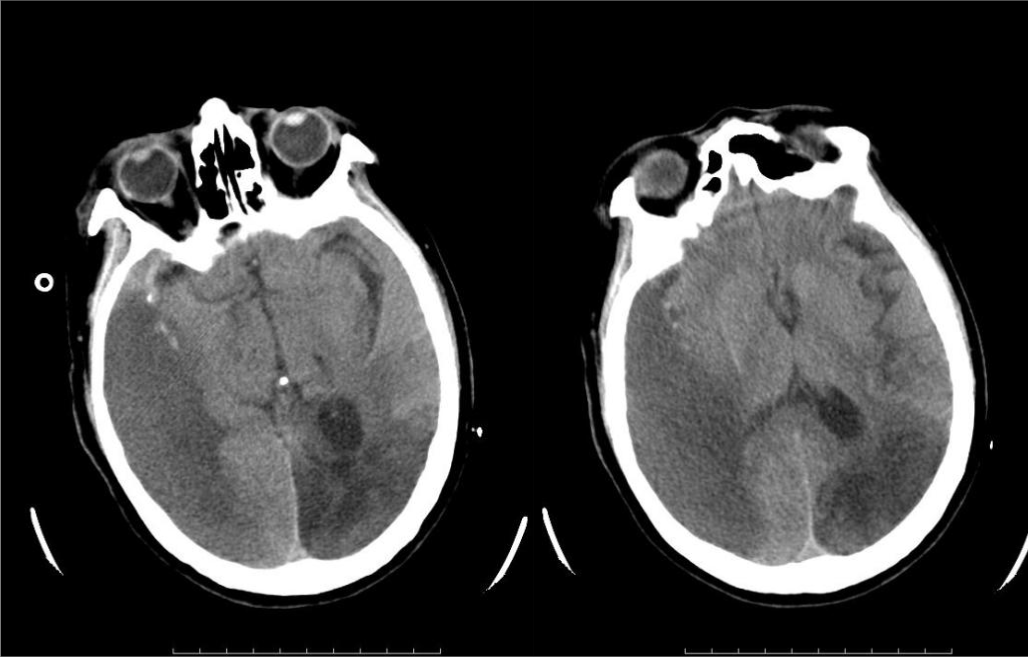

右侧大脑中动脉起始部闭塞,右侧大脑中动脉开通,取出血栓。

左侧大脑中动脉发出颞前动脉后远端闭塞,左侧大脑中动脉开通,取出血栓。

大脑中动脉M1段分叉部以远闭塞,大脑中动脉上干开通,取出血栓。